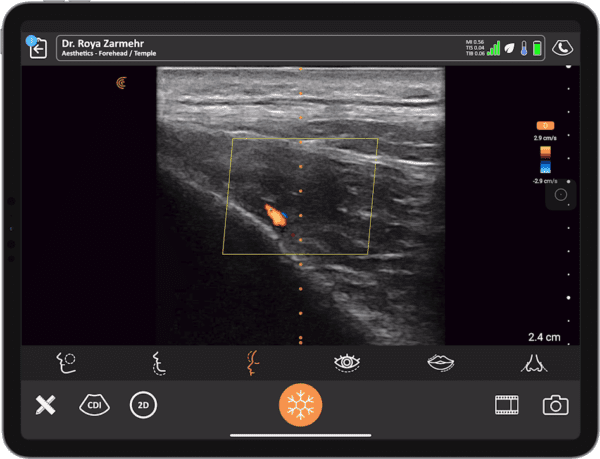

Ultrasound for Facial Aesthetics: Practical Tips to Simplify Facial Ultrasound

Curious about how ultrasound can enhance your facial aesthetics practice? Join Aesthetic physician and passionate ultrasound spokesperson Dr. Roya Zarmehr Zamin, for a practical webinar designed to streamline your facial ultrasound workflow, with the ultimate goal of enhancing safety and improving outcomes in aesthetic procedures.

- Techniques to quickly identify important facial vessels, with and without Doppler

Live scanning demonstrations will be performed with the Clarius L20 HD3—our ultra-high frequency scanner designed specifically for facial aesthetics—showing you exactly how these techniques work in real-time.